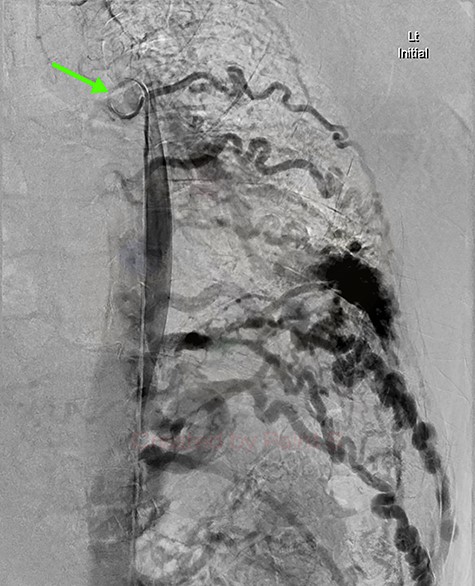

DSA utilizing superselective catheterization to demonstrate contribution to the PAVM via the left inferior phrenic artery, and its extensive subdiaphragmatic collateralization.

Given the findings, he was referred to Interventional Radiology for a formal digital subtraction angiogram with view of transcatheter embolization. Under local anaesthetic and sedation, a 5-french sheath was placed in the left common femoral artery. Using a 5-french pigtail catheter, aortic angiography was undertaken, confirming the CTPA findings and demonstrating predominant supply of the vascular malformation via the left intercostal arteries and the left inferior phrenic artery (Fig. 4)—draining into the left inferior pulmonary artery and vein. Superselective catheterization of the left intercostal arteries (Fig. 5) and the left inferior phrenic artery (Fig. 6) are shown. Unfortunately, due to the malformation’s volume and complexity, embolization was abandoned. He was subsequently referred to Cardiothoracic Surgery, currently awaiting consideration and workup for ligation and resection via video-assisted thoracoscopy, and potentially thoracotomy.